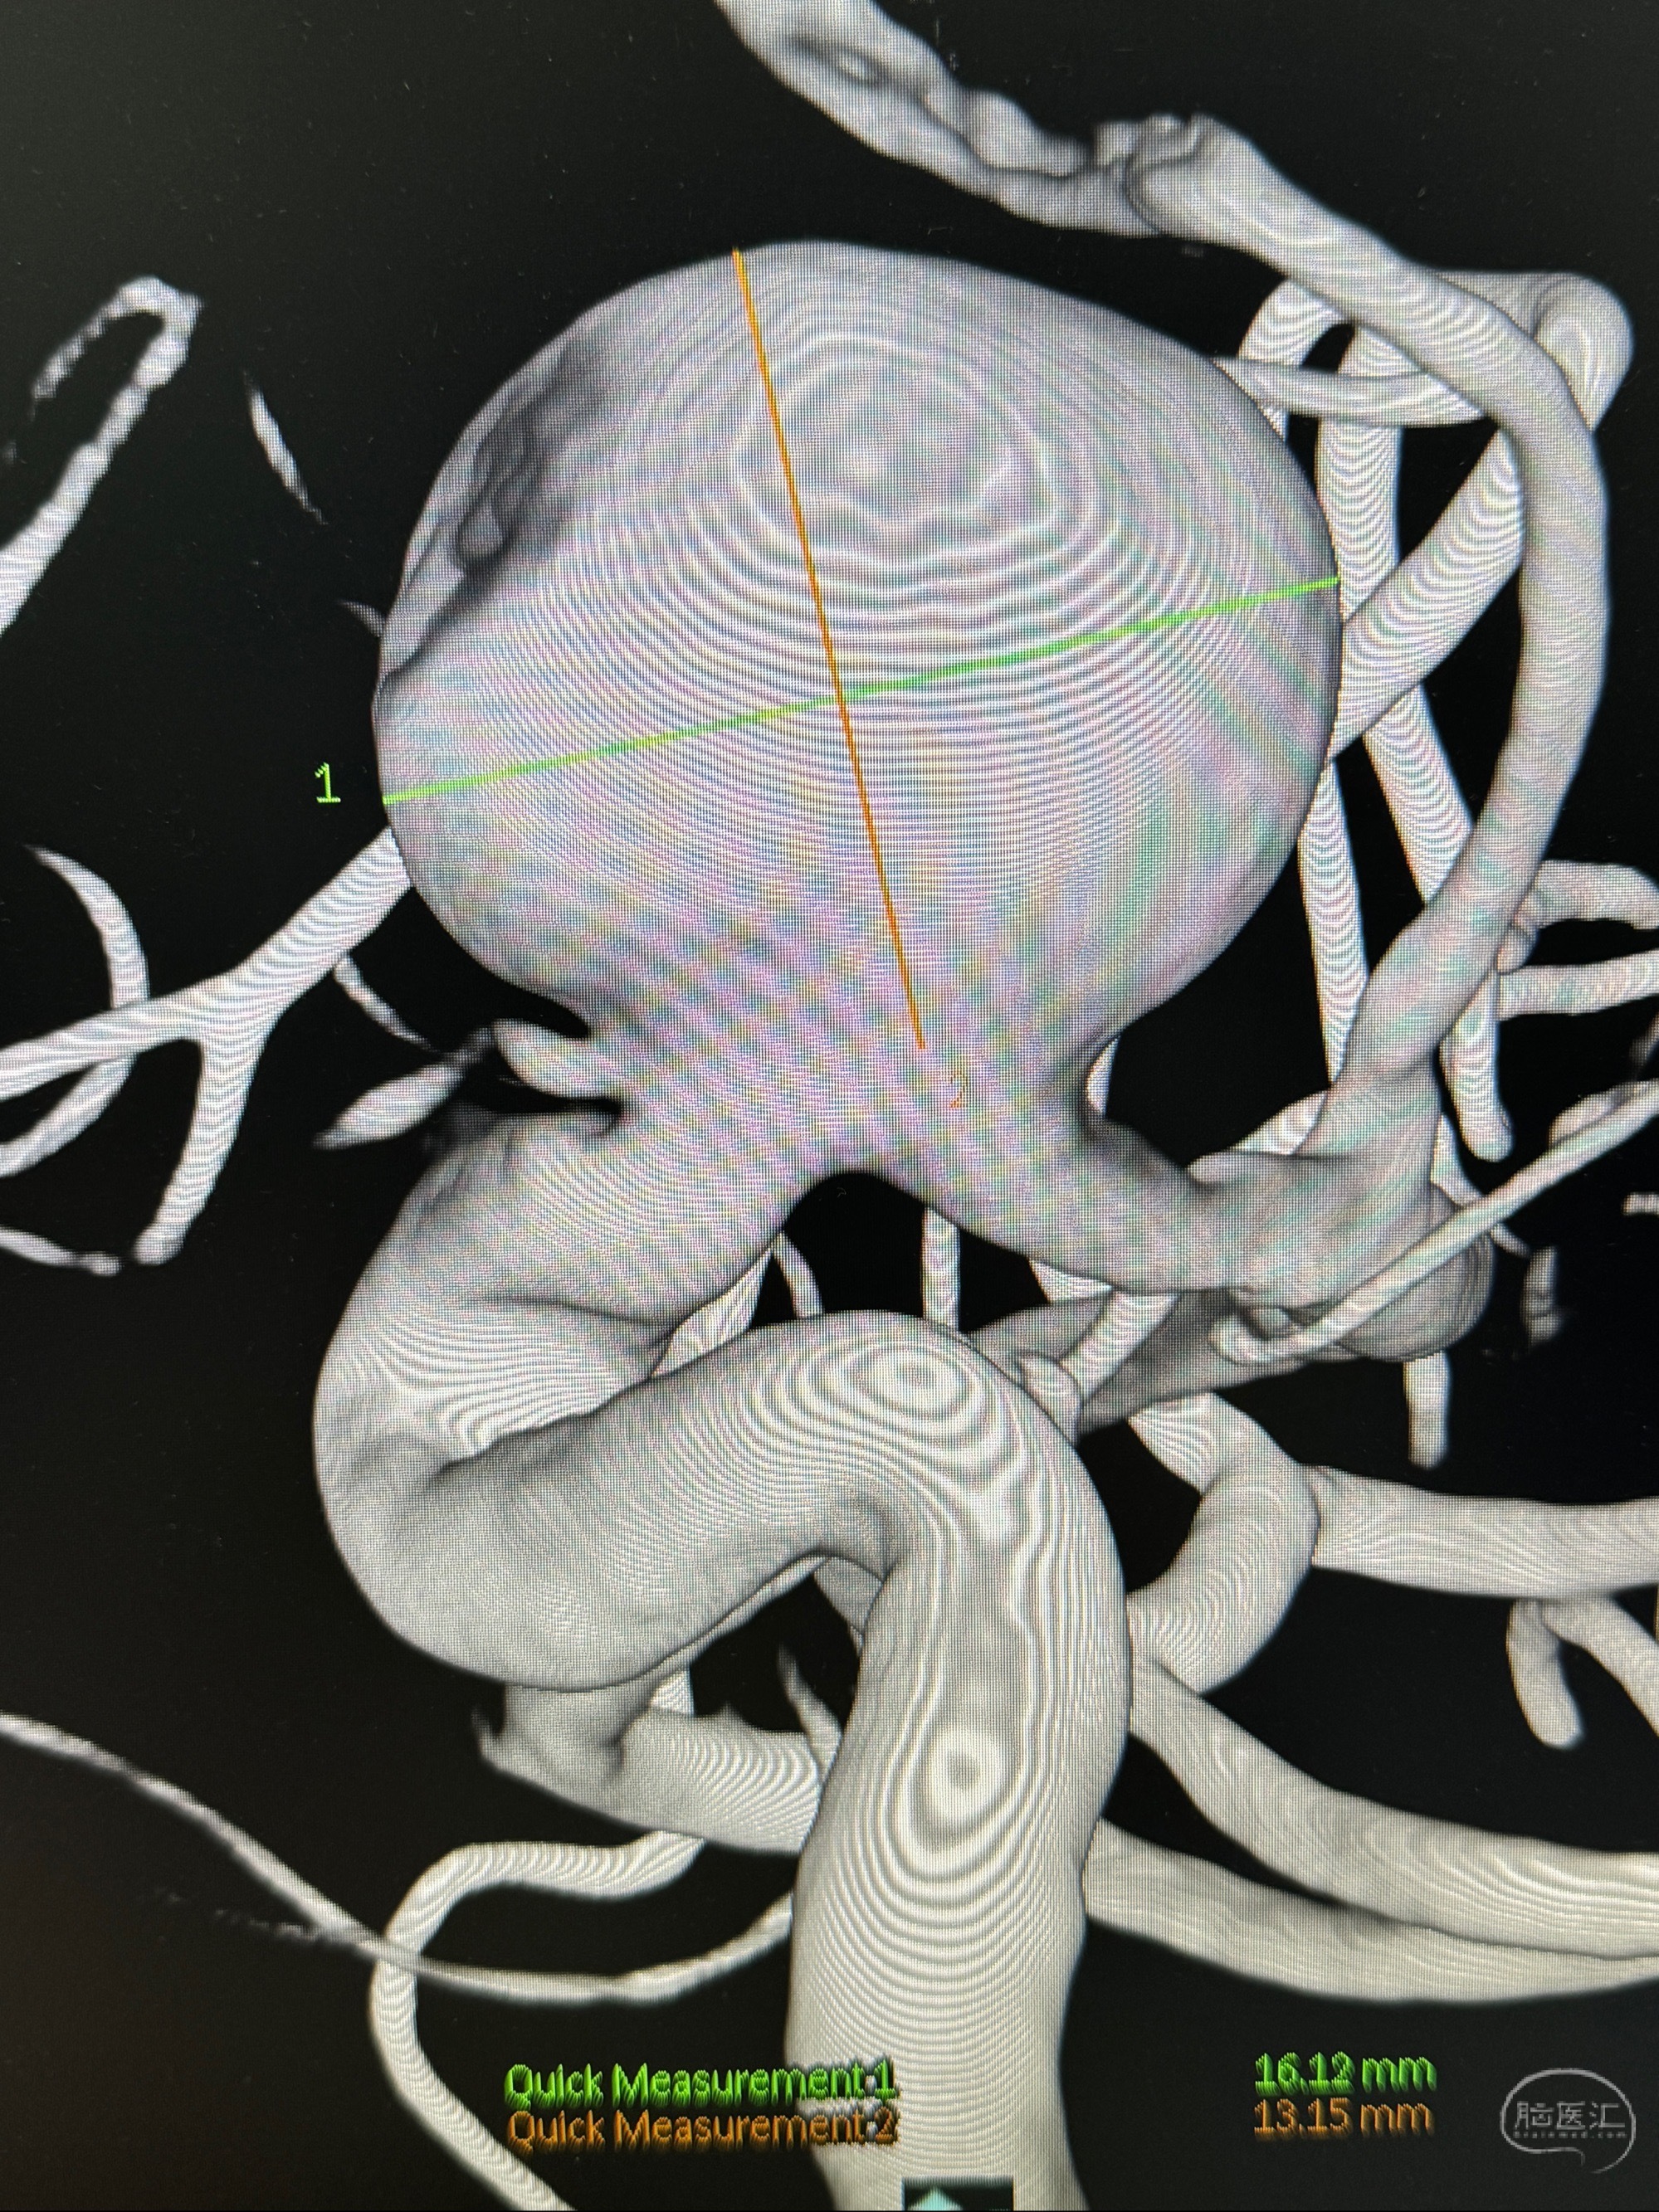

旋转3D展示动脉瘤局部的血管构筑

测量动脉瘤的大小:16*13.8*7.6mm大小,较原先变大,考虑双抗后瘤内血栓溶解可能

观察动脉瘤腔内的血流动力学情况